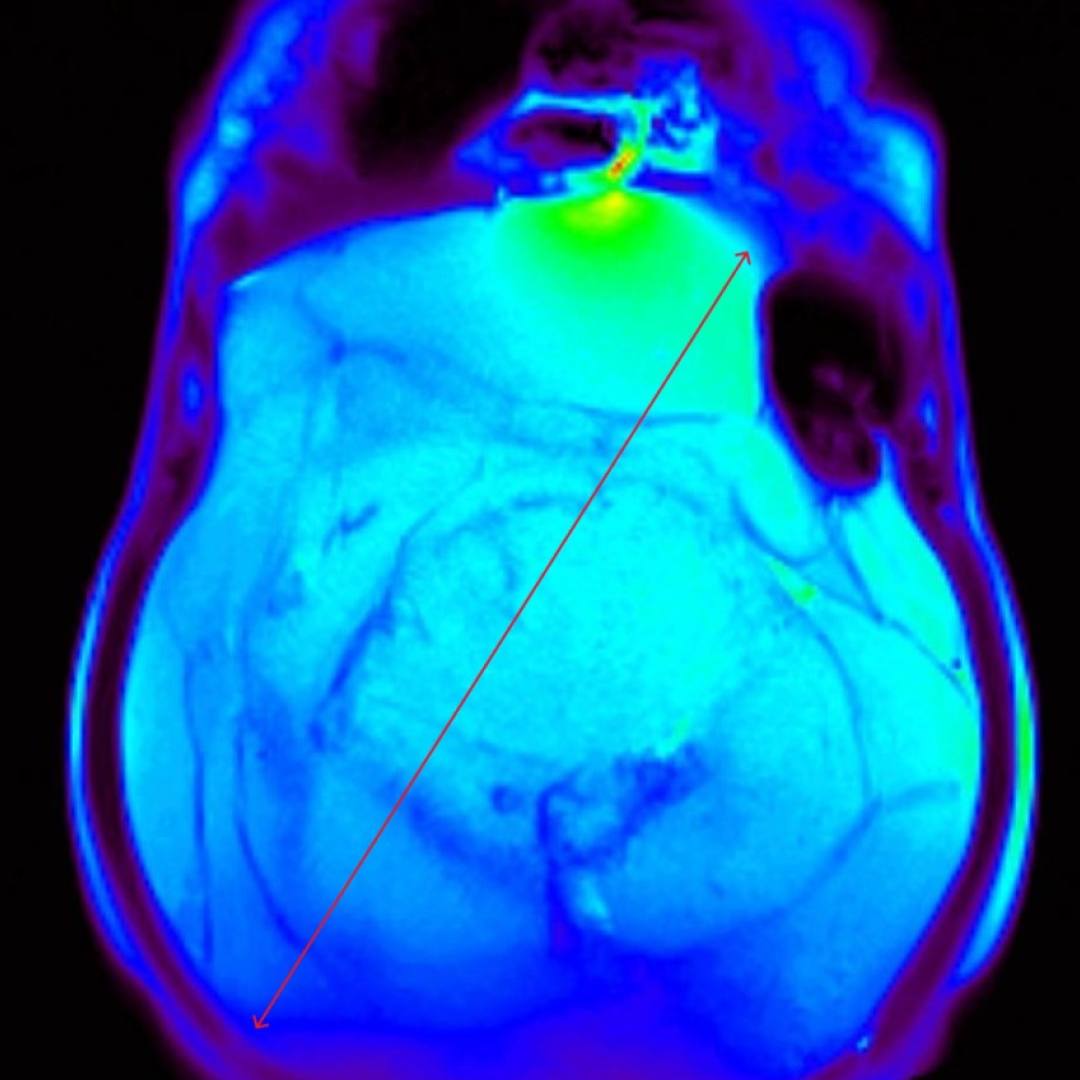

С целью оценки образования, а также уточнения расположения и взаимоотношения с органами брюшной полости проведено МРТ органов брюшной полости с внутривенным контрастированием.

При МРТ было выявлено жиросодержащее внеорганное объемное образование больших размеров с множественными неравномерными накапливающими контрастный препарат перегородками, занимающее большую часть брюшной полости с признаками смещения прилежащих внутренних органов.

Учитывая особенности структуры образования, распространенность и расположение, находка расценена как липосаркома (злокачественная опухоль жировой ткани).